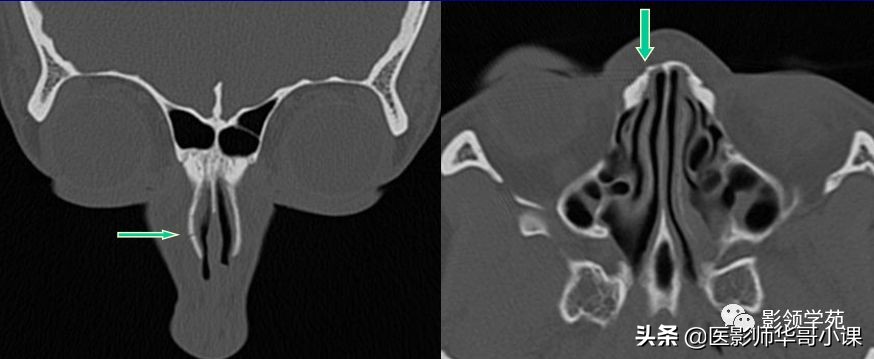

骨折HRCT表现

- 外形

- 骨折线

- 软组织肿胀、积气

- 邻近部位骨折

线性骨折 粉碎骨折

右侧鼻骨线形骨折

鼻骨线形骨折

左侧鼻骨线形骨折